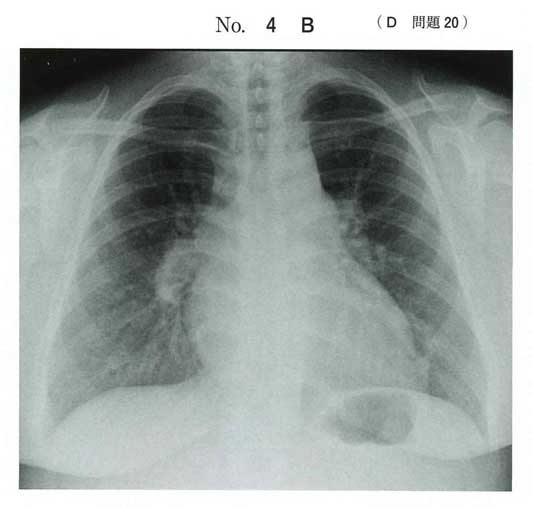

心電図はS1Q3T3、V1-4の右室負荷所見

若年女性なので膠原病関連のPH、DVTやPE/CTEPHにしても膠原病はみたいところかと